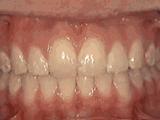

牙列拥挤,牙槽骨过窄,牙齿没有足够空间,只好前后左右高低上下乱长,经过矫正后的牙齿是这样的~